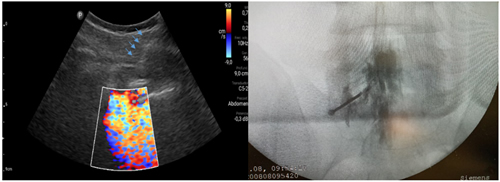

Fig. 1. Escaneo ecográfico en eje corto o transversal del espacio L5-S1. La flecha amarilla muestra el punto de entrada de la aguja de Touhy en el abordaje paramedial y su trayecto. A la derecha se muestra la colocación de la aguja Sono Touhy en plano con el transductor curvo.

Fig. 2. Inyección de 5 a 10 ml de suero fisiológico con registro de la imagen doppler color, que se distribuye en el canal raquídeo, en una inyección epidural L5S1 paramediana derecha (imagen a la izquierda). Las flechas azules indican el trayecto de la aguja de Touhy. A la derecha se observa la confirmación con epidurograma de una inyección epidural L5S1 izquierda.